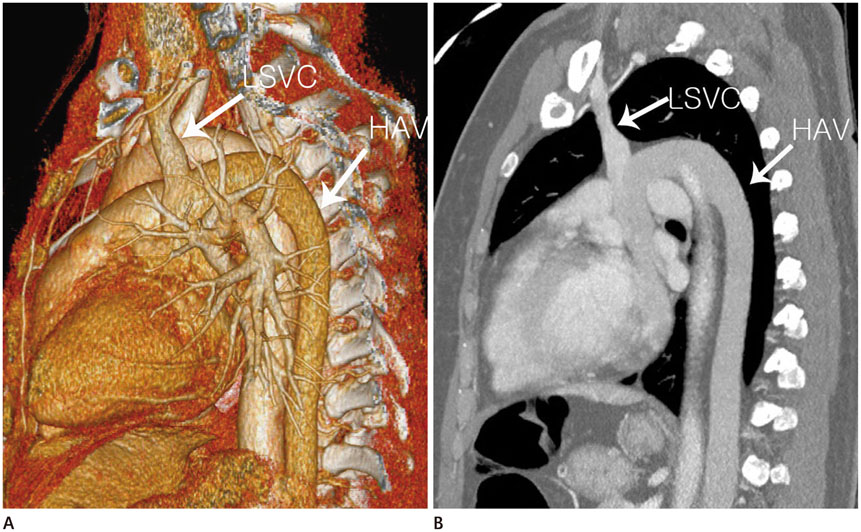

Interrupted Inferior Vena Cava with Hemiazygos Continuation in an Adult with a Persistent Left Superior Vena Cava and Left Single Coronary Artery: A Case Report

A 50-year-old woman was referred to our institution for medical screening due to an incidental finding on abdominal ultrasonography. She underwent chest, abdomen and cardiac multi-detector computed tomography (MDCT). Her MDCT revealed absence of the hepatic segment of the inferior vena cava (IVC), with hemiazygos continuation and a left single coronary artery. The dilated hemiazygos vein drained directly into the persistent left superior vena cava (SVC). Herein, we reported a very rare case combining an incidentally found interrupted IVC with hemiazygos vein continuation, persistent left SVC and a left single coronary artery diagnosed by MDCT.